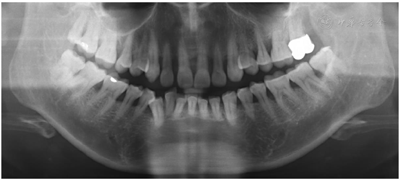

12年后复查时,口腔卫生状况良好,牙龈色偏粉,全口探诊4~6 mm,后牙区个别位点7~9 mm,探诊出血阳性率(89.3%比55.3%)和PD≥5 mm(38.6%比24.4%)百分比均下降,全景片显示牙槽嵴顶骨白线清晰、连续。

完善的牙周基础治疗可以控制绝大多数的牙周炎症,在重度牙周炎的病例中,也可获得良好的治疗效果[5,6]。本病例中经过12年的治疗,影像学显示牙周状况稳定,但对于后牙区垂直型骨吸收应尽早进行牙周手术治疗;另一方面考虑26烤瓷冠对邻面骨吸收的影响。

本病例中患者在经过1轮完善的牙周基础治疗后症状明显改善,自此于外院门诊行长达7年的洁治术。与7年前相比,可见牙槽骨有明显的降低。之后每年定期进行牙周维护治疗,可见牙槽骨硬骨板出现,连续。

该病例历经12年的牙周随访治疗,影像学显示牙槽骨维持稳定,患者16、26、36、46仍可探及深牙周袋,与患者反复沟通后,考虑行引导组织再生术以期获得牙周组织再生。